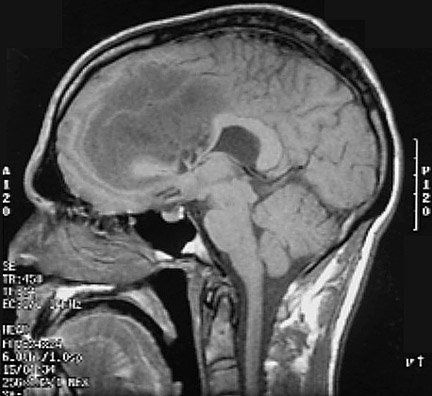

This is a sagittal MRI scan demonstrating a large glioma impinging upon the ventricular system. A transverse view is shown below

Click on the glioma in the MRI scan below: